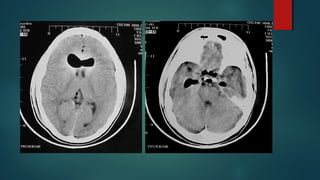

Este documento es el programa para un taller de imágenes del curso de emergencia 2015 impartido por el Dr. Víctor Delgado. El taller se centra en el uso de imágenes médicas para el diagnóstico y tratamiento de pacientes en coma traumático según la base de datos de Marshall. El Dr. Delgado es el único instructor repetido a lo largo del documento.